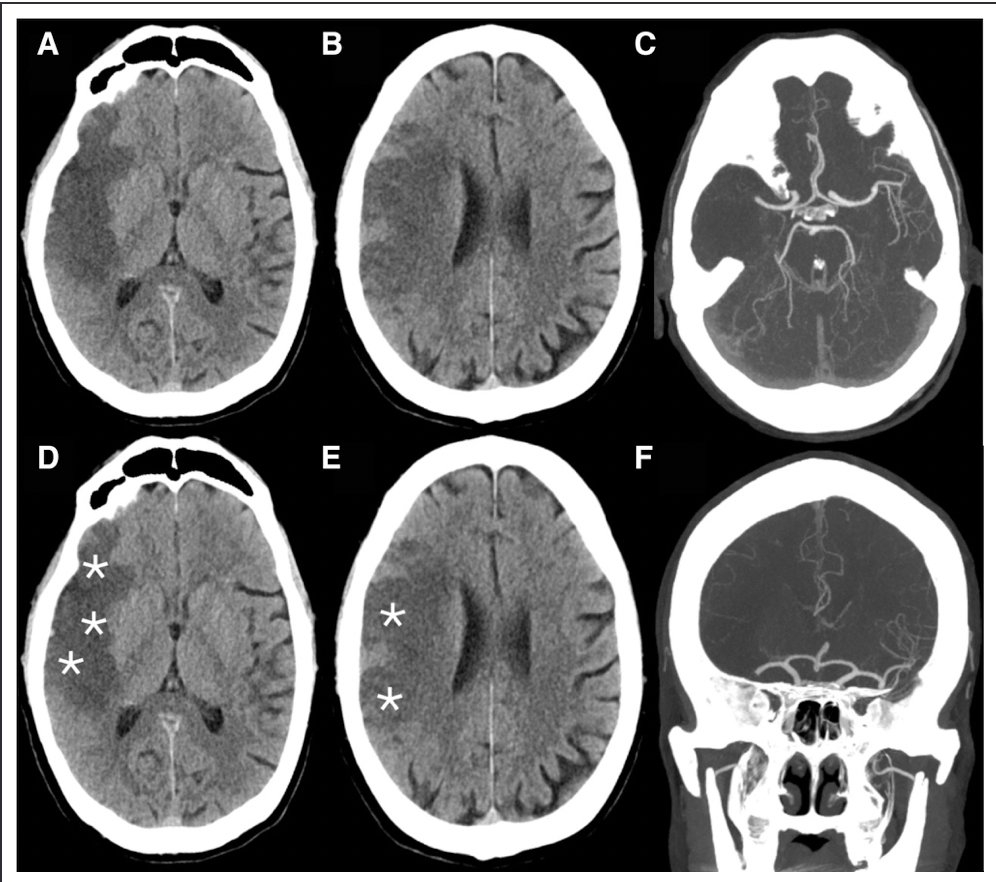

Clocchiatti-Tuozzo et al: Different Responses to Blood Pressure Reduction in Lobar and Deep Intracerebral Hemorrhage Link: link.springer.com/article/10.100… @neurocritical #neurocritcare